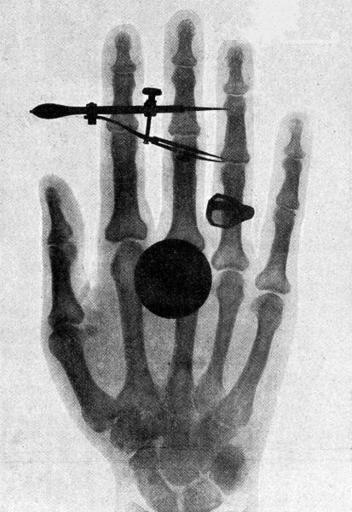

| View Original: | Wilhelm-Roentgen's-X-ray-photograph-of-his-wife's-hand.png (413x600) | |||

| Keywords: Wilhelm-Roentgen's-X-ray-photograph-of-his-wife's-hand.png Wilhelm Roentgen's X-ray photograph of his wife's hand http //www brockhaus-multimedial de/cgi-bin/dpalink/dpacopy pl necessary R F6ntgen optional Conrad+Lennep+Hohenheim+Remscheid+R F6ntgenstrahl+W FCrzburg+Gie DFen+X+Stra DFburg+Physiknobelpreis theme 52 product bmm2008 session 1196369016-28841 method NOT page 1 bigview 4 set 2 lock 1328122 Brockhaus multimedial- Einzelbild aus dem DPA Bildarchiv 1896 Wilhelm Conrad Röntgen This image is in the public domain because the author is dead for more than 70 years PD-old X-rays with wedding rings Radiographs by Wilhelm Conrad Röntgen | ||||